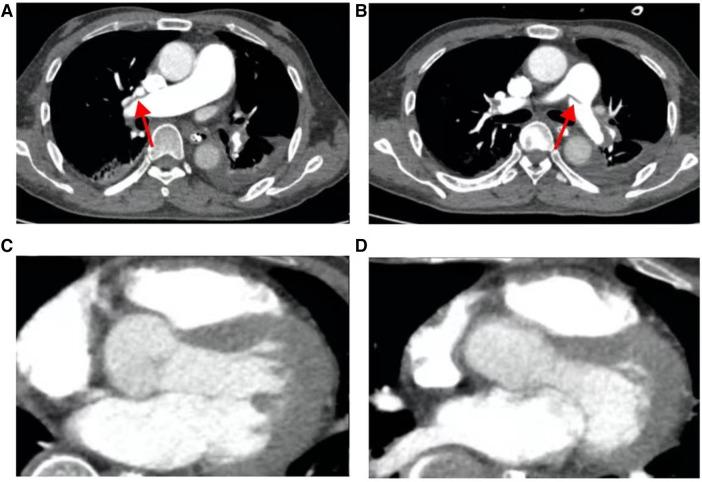

METHODS

This report presents the case of a 52-year-old male admitted due to fever and sudden onset of impaired consciousness, with cardiac ultrasound and pulmonary artery CT angiography revealing an acute large-scale pulmonary embolism accompanied by bilateral atrial thrombosis, with the condition rapidly worsening and manifesting severe respiratory and circulatory failure. With ECMO support, the patient underwent a thrombectomy using an AngioJet intervention. The diagnosis of CAPS was confirmed through clinical presentation and laboratory examination, and treatment was adjusted accordingly.